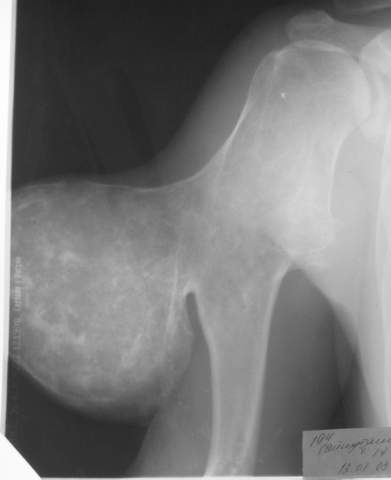

Вот, пришел сегодня утром на работу,фотоаппарат зачем то прихватил.ни о чем таком не думал,а там такоое...:-)

Мужчина, 27 лет, IQ вроде бы нормальный, из района, но не из деревни, а такую штуковину вырастил... аж жуть...

А каков Ваш диагноз?

По-моему больше всего похоже на вторичную хондросаркому (озлокачествленный костно-хрящевой экзостоз плеча).

Похоже

Что это озлокачествленный экзостоз - очевидно...

Но тактика лечения при любых раскладах одна - удалять.

Skoree vsego хондросаркомa вторичнaя, na osnove Multiple osteochondomatosis.